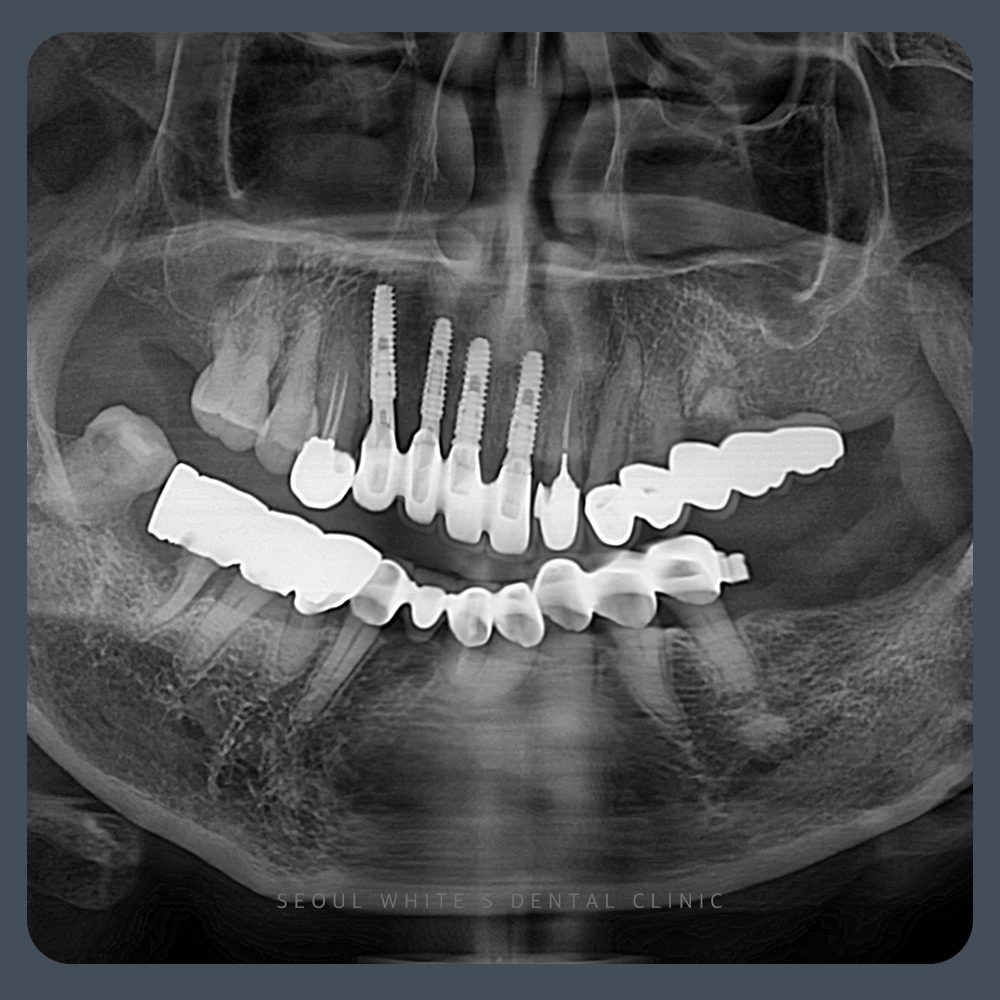

술 전

2022.09.17

이 환자분의 경우, 좌측 상악과 우측 하악에 상태가 좋지 않은 브릿지가 여러 개 확인되었습니다. 또한 좌측 하악의 보철물은 형태를 수정해야 하는 상황이었습니다. 따라서, 하악 전치부와 같은 보존 가능한 부위는 가능한 한 오랫동안 사용할 수 있도록 유지 관리할 계획을 세웠습니다. 반면, 예후가 좋지 않은 브릿지는 모두 제거하고 새로운 치료 방법을 진행하기로 하였습니다.

또한 좌측 치아 부위는 이전에 자연치가 상실된 지 시간이 꽤 지난 상태였습니다. 이번 임플란트 식립 시, 기존 보철물의 형태를 조정하면서 두 개의 임플란트를 함께 식립하여, 어금니 부위의 저작 기능을 회복할 수 있도록 계획하였습니다. 앞서 말씀드린 치료 계획은 모두 진행되었으며, 이어서 시술 후 관리와 경과에 대해서도 안내드리겠습니다.